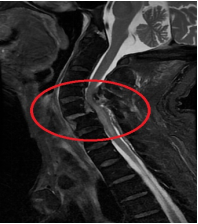

全力做好术前准备。患者入住骨科后,颈椎核磁共振证实“颈部脊髓损伤(颈4-6平面)、颈椎硬脊膜血肿(颈5、6平面)”。因合并“胸7椎体压缩骨折、左侧多支肋骨骨折(2、6、7)、胸骨骨折、肺部感染、高血压病、低钠血症”,且存在压疮、深静脉血栓等高危因素,病情复杂且危重,骨科医护团队第一时间启动心血管内科、麻醉科等多学科MDT联合会诊,积极完善术前检查、防治肺部感染、压疮、深静脉血栓、关节僵硬、营养不良等并发症,力争将患者身体状态调整到尽可能安全水平的。

精准完成复杂手术。在充分术前准备基础上,3月19日省医-阿医骨科专家联合、由省医院脊柱外科张伟教授主刀,在患者全身麻醉状态下,为其精准施行“经前路颈5/6脱位切开复位钉板系统内固定术、椎间盘切除、椎管减压、Cage植入椎体间融合术+经后路颈3-7钉棒系统内固定术(8钉2棒)、椎管扩大减压、横突间植骨融合术”。手术顺利,术后右下肢肌力恢复至3级,右上肢肌力恢复至2+级。